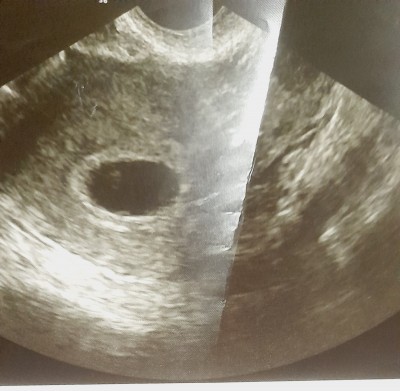

Arkadaşlar 13 mayısta  gidince böyleydi ultrasyon kağıdım pazartesi gidicem böyle olup sonra bebeği gören oldumu

Gebelik haftası 8

Birebir aynı ultrason fotoğrafı neredeyse benimki 6 haftalıkken gitmiştim ilk böyleydi bebek görünmemişti sadece kese vardı 2 hafta sonra gel demişti doktor 2 hafta sonra hem bebeği görmüştüm hem kalp atışını duymuştum

Evet cnm çok şükür duydum gittiğimde 9+2 günlükte 7+4olarak göründü geç dollenme olmuş dedi